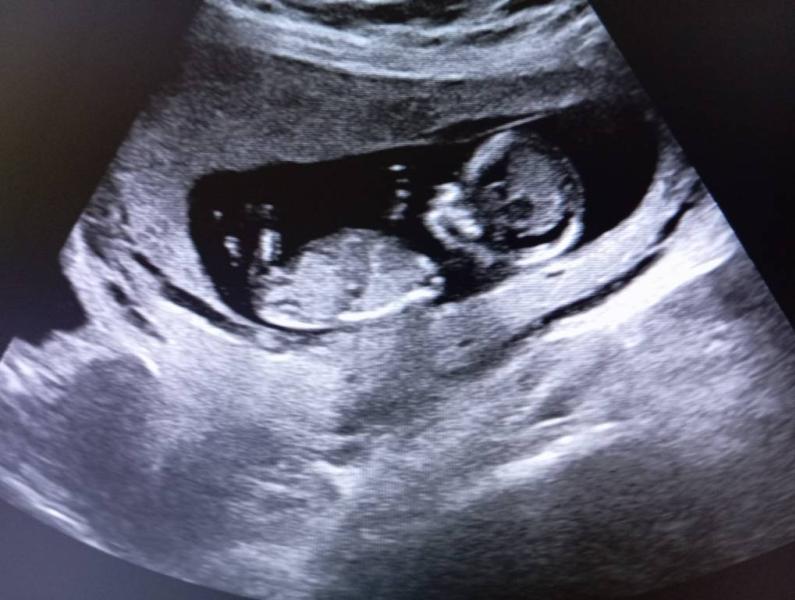

С утра поехала на УЗИ с дочкой)) Она была под впечатлением, сняла видео 😍 по УЗИ всё хорошо, срок даже чуть больше, 12 недель 4 дня, уже видно ручки, ножки, позвоночник, мозг) Двигается, всё хорошо, ттт!

Я очень конечно обрадовалась. Ну совсем хорошо, подрастает! 🥰